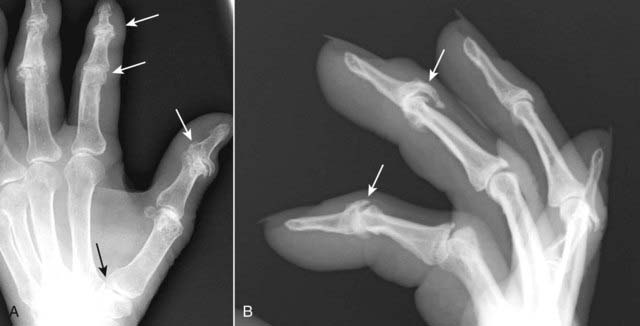

Figure 23-13 Rheumatoid arthritis, hand (A) and wrist (B).

A, In the hand, the erosions of RA tend to involve the proximal joints: the carpal-metacarpal joints, metacarpal-phalangeal (solid white arrows), and proximal interphalangeal joints. Late findings in the hands include deformities such as ulnar deviation of the fingers at the MCP joints, subluxation of the MCP joints, and ligamentous laxity leading to deformities of the fingers, which are also present in this hand. B, In the wrist, erosions of the carpals (dotted white arrow), ulnar styloid (solid white arrow), and narrowing of the radiocarpal joint space (solid black arrow) are commonly seen.